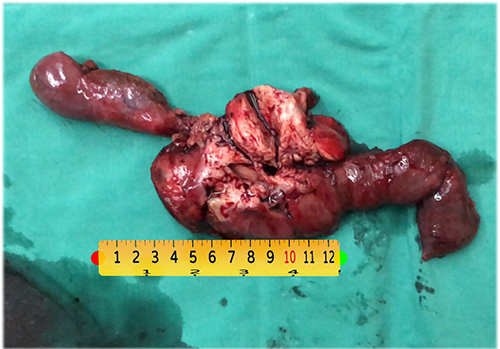

慢性胰腺炎伴假性囊肿形成